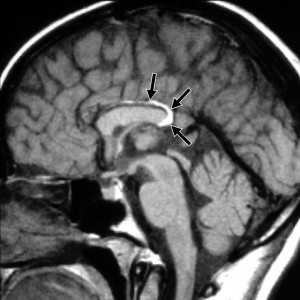

МРТ головного мозга. Сагиттальная Т1-взвешенная МРТ. Липома мозолистого тела.

МРТ головного мозга. Сагиттальная Т1-взвешенная МРТ. Пинеальная киста.